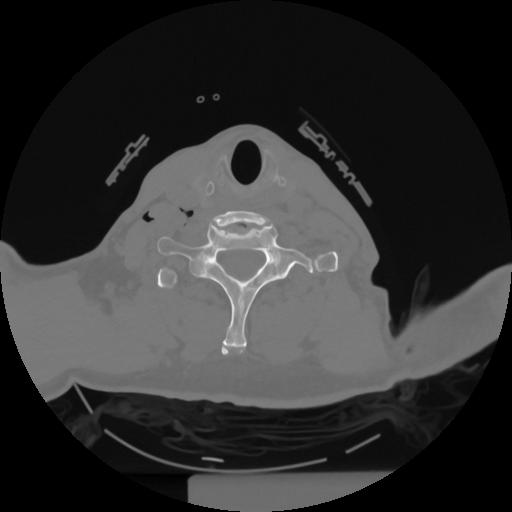

12 P.BLANDAS,,Vol,0.5,P.BLANDAS,,